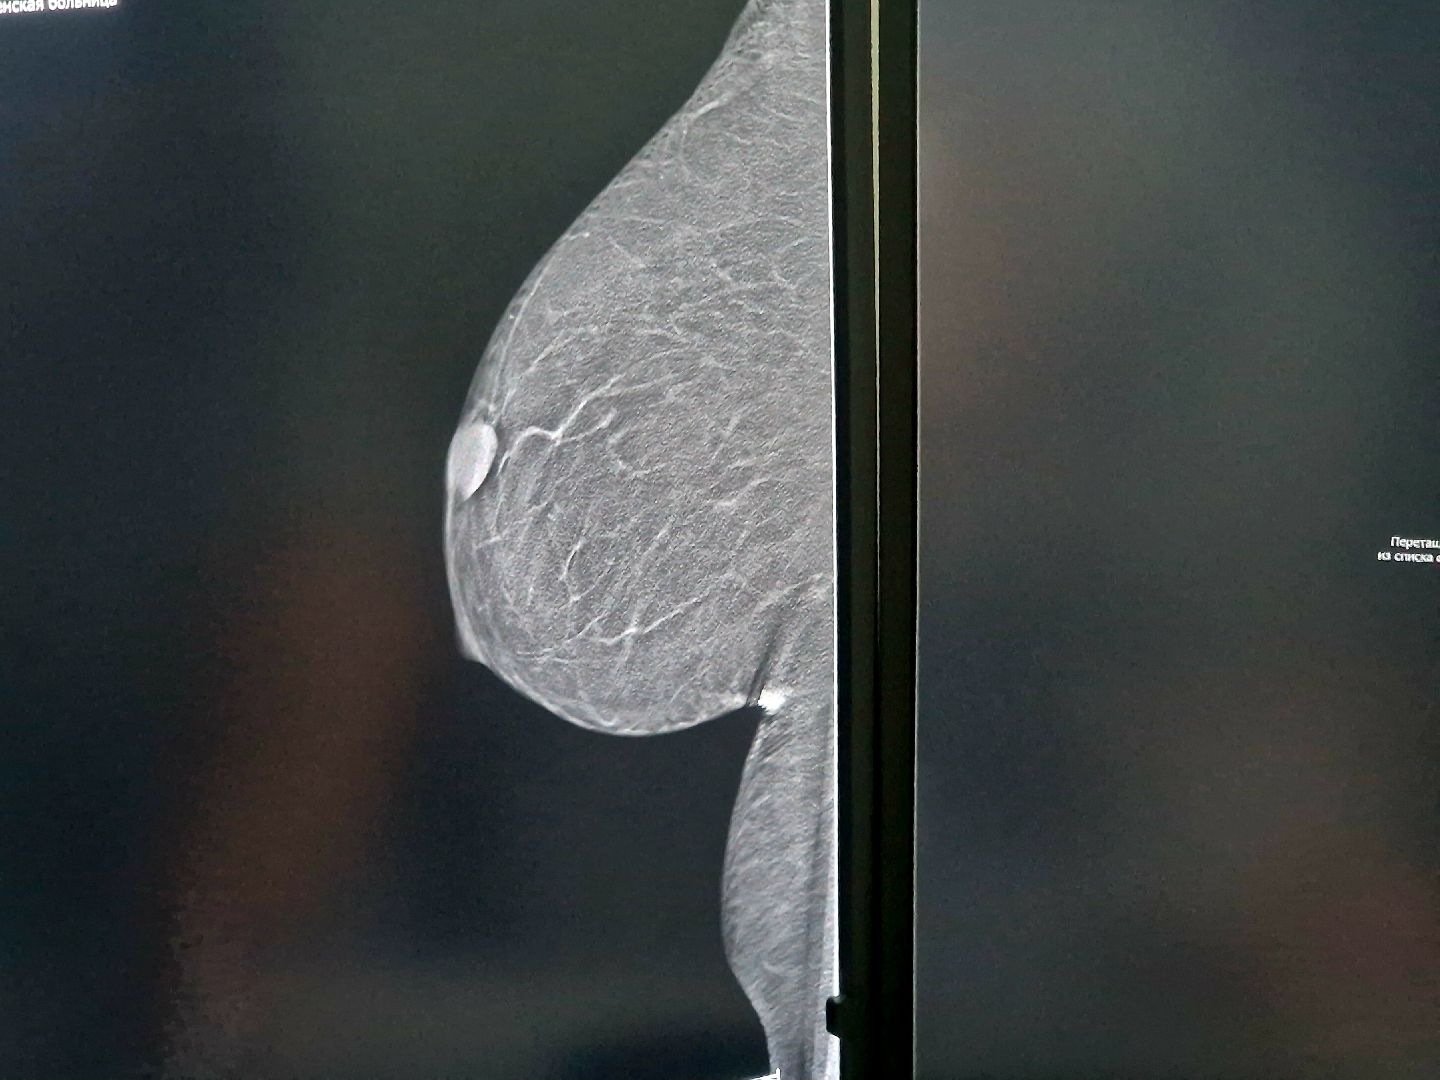

Главный результат профилактических осмотров — выявление тяжёлых болезней на ранней стадии. «В этом году только в Центре здоровья мы обнаружили три случая рака молочной железы, три — прямой кишки, а также по одному случаю онкологии печени, кожи и лёгких. Все эти пациенты успешно лечатся, и сейчас их состояние в норме», — сообщила Татьяна Власова.

Пройти диспансеризацию жители Воскресенского округа могут в Центре здоровья по адресу: Больничный проезд, д. 3, корпус 3. Процесс организован удобно: все обследования — от анкетирования и измерения давления до ЭКГ и маммографии на современном оборудовании — можно пройти в одном здании примерно за час. Предварительная запись не требуется, услуги оказываются бесплатно по полису ОМС.